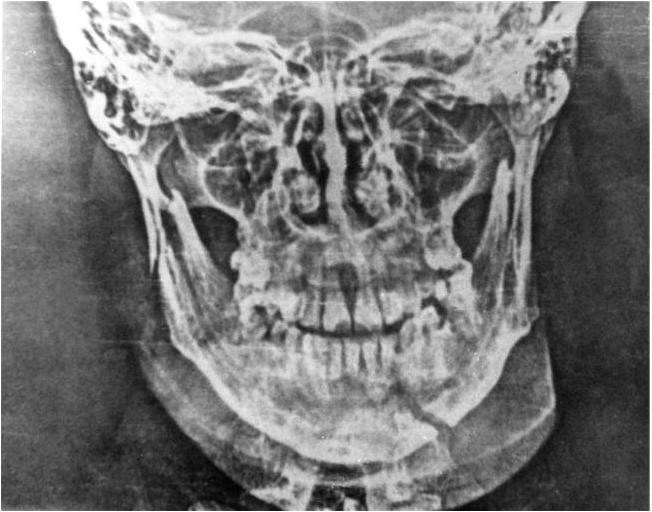

В настоящее время широкое распространение получил метод рентгенографии без использования рентгеновской пленки – электрорентгенография. Получаемые при этом изображения нижней челюсти вполне удовлетворяют требованиям диагностики (рис. 6), а простота и возможность быстро получить отпечаток делают этот метод очень перспективным, особенно для военно-полевой челюстно-лицевой хирургии.

Рис. 6. Электрорентгенограмма нижней челюсти при переломе в области основания мыщелкового отростка справа и |34 зубов